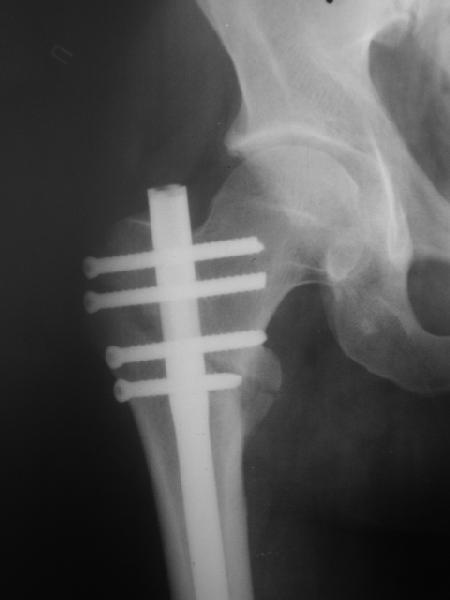

В частности, на проксимальном конце сделано еще одно дополнительное статическое отверстие. Можно ввести в проксимальном отделе 4 винта, из них 3 статические (2 в круглые отверстия и 1 по нижнему краю овального). Картинки в приложении. На дистальном конце стержня тоже кое-что улучшено. Спрашивайте в аптеках, как говорится. Выпускается предприятием "ЦИТО" (Москва), то есть это малобюджетное решение.

Конечно, мы не синтезируем остеопорозые вертельные переломы согласно прилагаемому примеру, винты 6 мм вырежутся. Но у более молодых при хорошем качестве кости такие или подобные гвозди с поперечным расположением винтов вполне применимы для меж- и подвертельных переломов.

Это было года 2,5 назад, мы тогда еще уточняли возможности шинирования с угловой стабильностью гвоздем с поперечным расположением винтов при переломах проксимального отдела бедра. Пациенту не пришлось приобретать намного более дорогой рекон или проксимальный гвоздь. В приложении еще несколько примеров применения того гвоздя при высоких переломах бедра, в том числе с более латеральной точкой входа. Гвоздь изгибаем для этого.